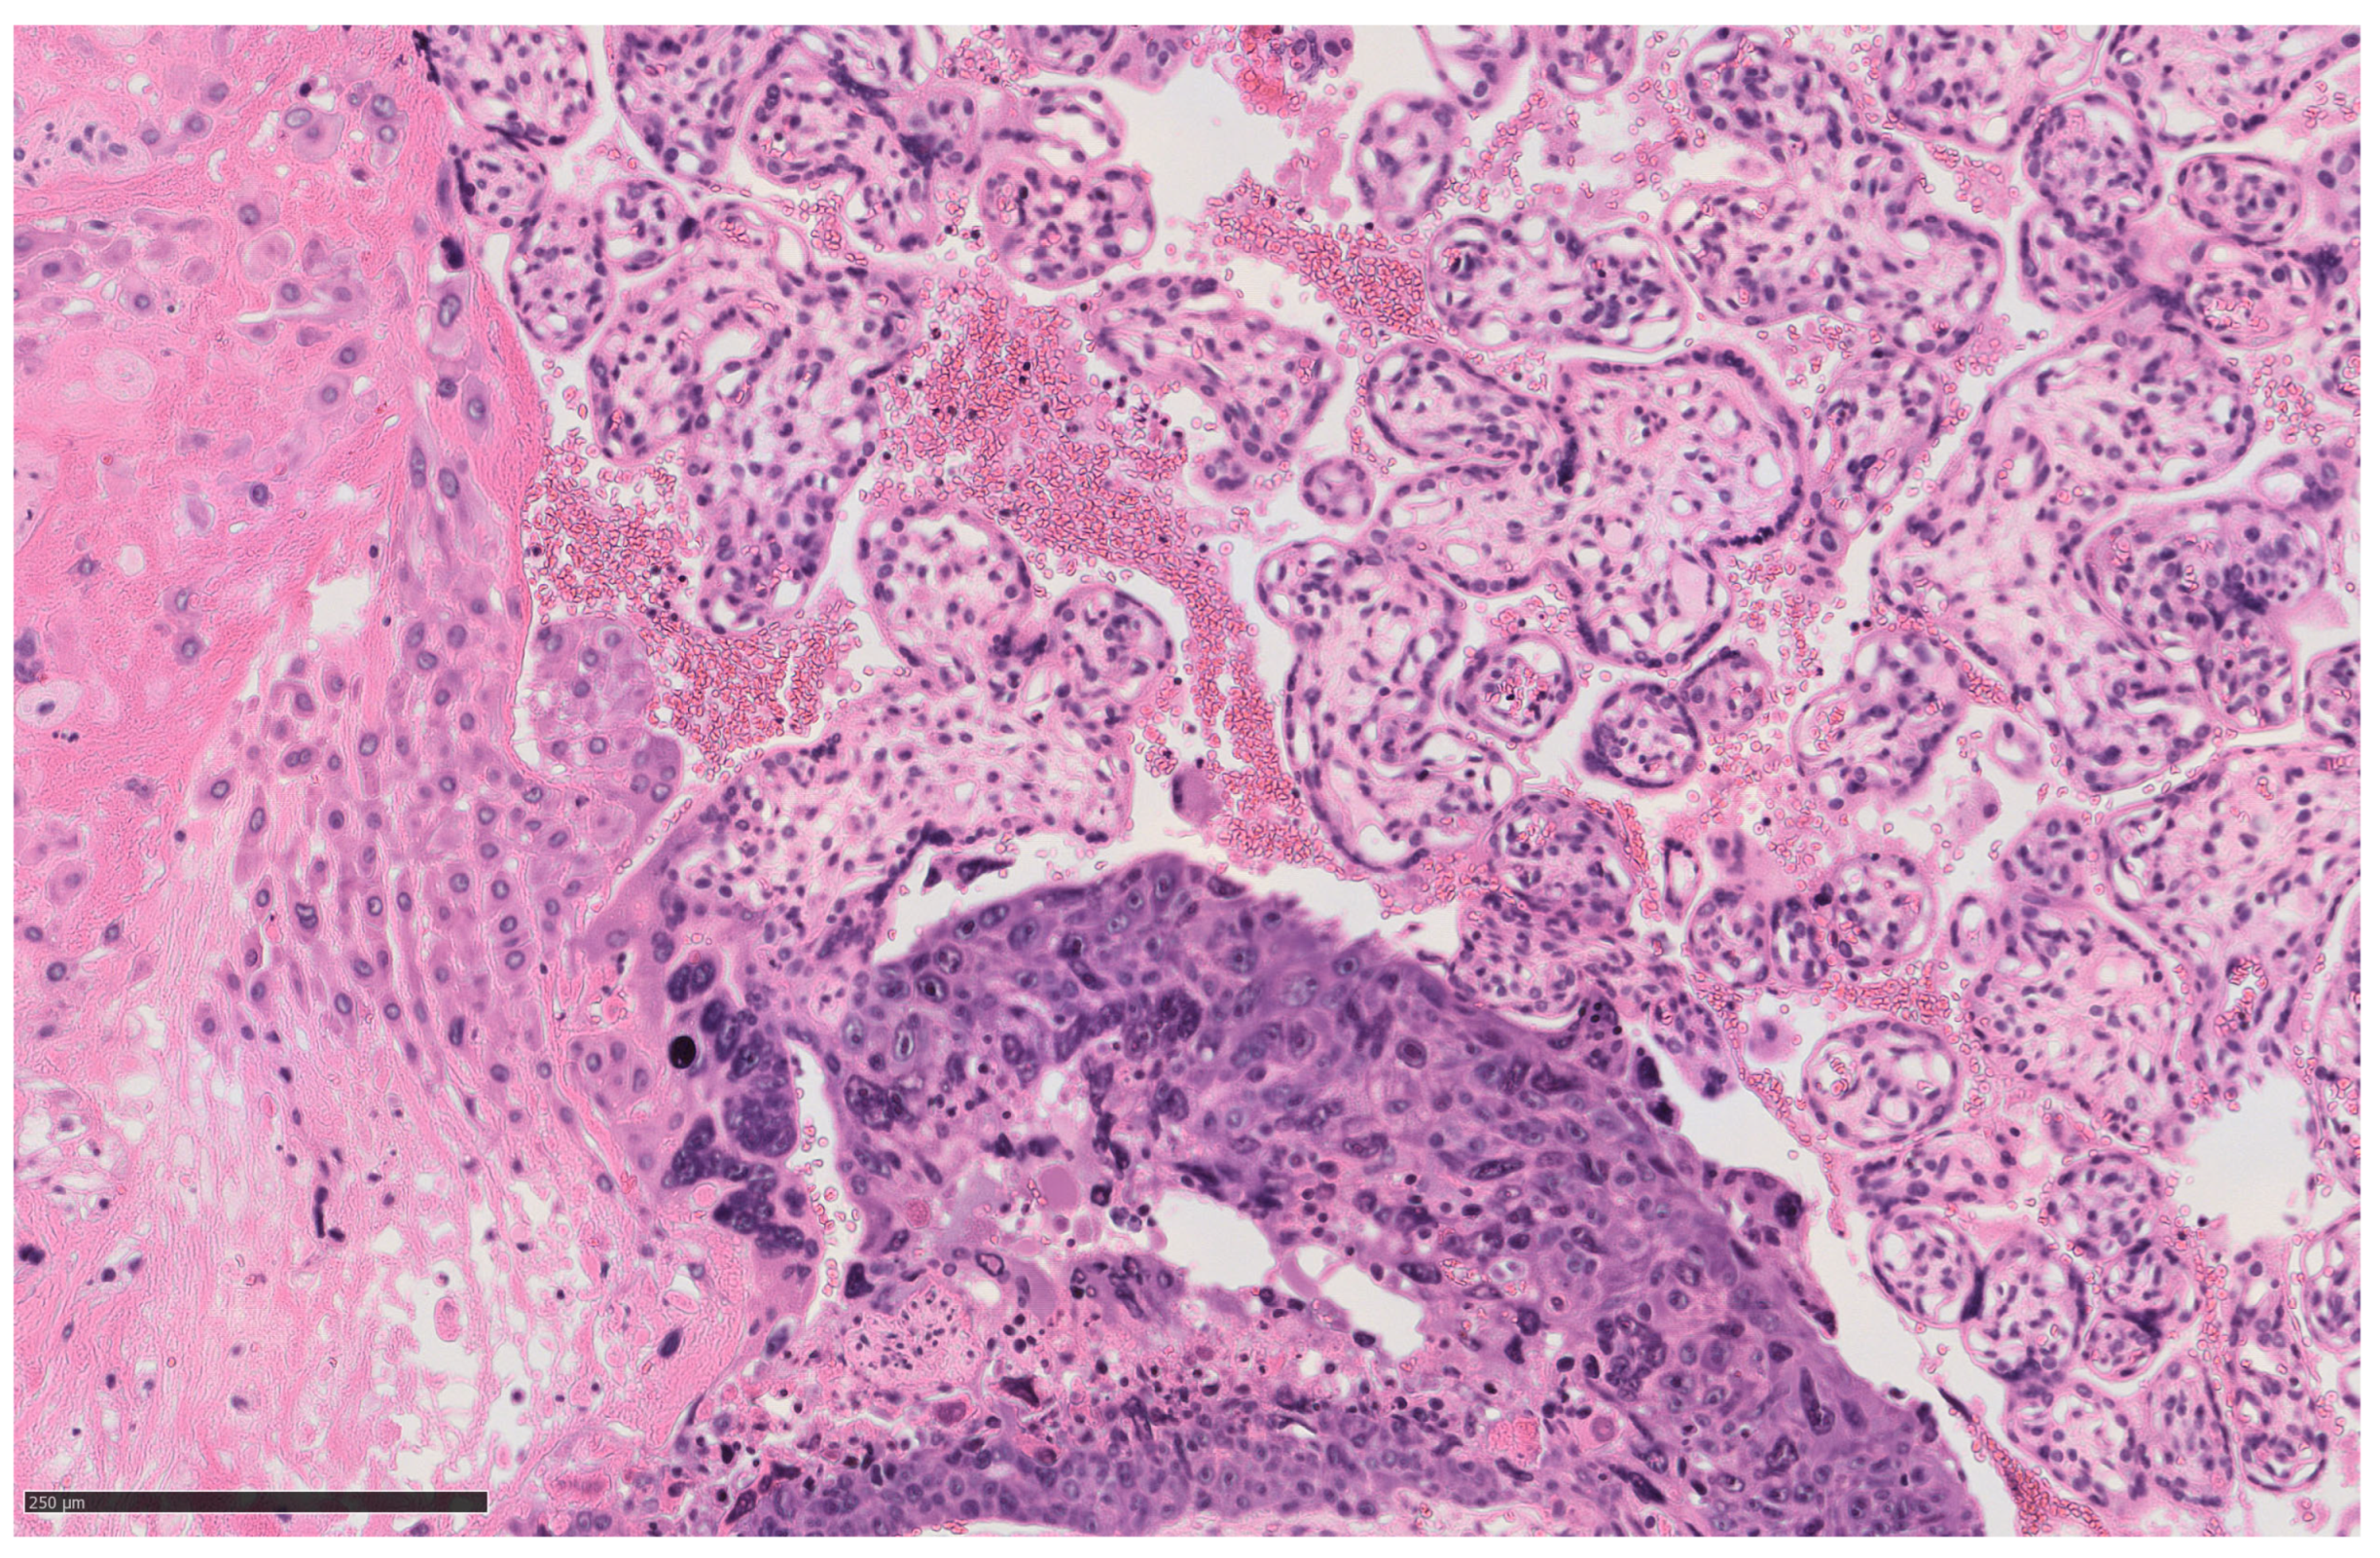

2. Case Description